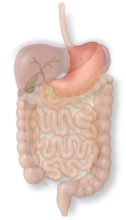

The gallbladder concentrates and stores bile as a pear-shaped sac which it can release to help digestion after a fatty meal.

The gallbladder concentrates and stores bile as a pear-shaped sac which it can release to help digestion after a fatty meal.

The duodenum is a C-shaped tube that receives food from the stomach and prepares it for chemical digestion further along in the intestines.

The stomach is a muscular sac that is important for absorbing food and preparing food for further digestion.

The pancreas is a gland that produces chemicals for food break-down as well as a hormone system that regulates sugar.